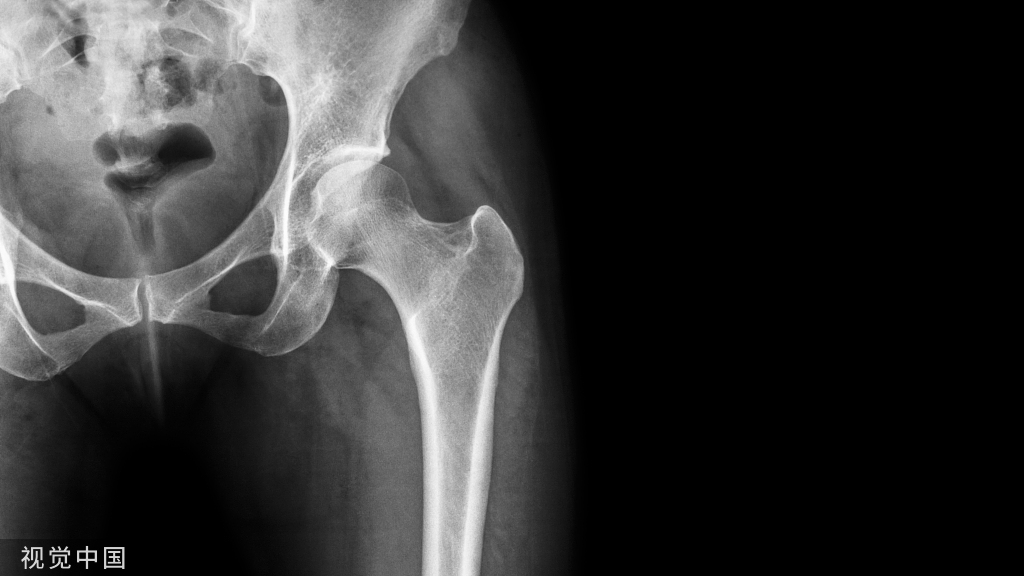

3、X线影像

髋关节正位和蛙式位是诊断股骨头坏死的X线 基本体位,通常在早期表现为硬化、囊变及“新月征”,坏死区与正常区域之间往往可见硬化征象等;晚期股骨头因塌陷失去原有球面结构,以及呈现退行性关节炎表现。

血运变化晚期(动脉闭塞期):动脉血管内皮增生增厚,动脉管径变小,甚至动脉结构缺 失进一步加大,完全进入动脉闭塞;股骨头塌陷的 范围和程度加大,表现为髋关节骨关节炎(图1)。